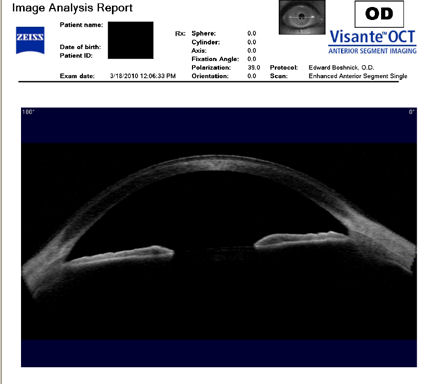

Следующие изображения были получены с использованием метода, называемого оптической когерентной томографией, или ОКТ. Прибор позволяет получить изображение в поперечном сечении путем сканирования передней части глаза (переднего сегмента) лучом света. Думайте об этом как об ультразвуке, использующем свет вместо звуковых волн для создания изображения живых тканей.

На изображении, приведенном непосредственно ниже, представлен снимок здоровой, неоперированной роговицы для сравнения со следующими изображениями эктатических роговиц после операции LASIK.

На изображении ниже представлен снимок роговицы в поперечном сечении после операции LASIK. Белая изогнутая линия вверху - это передняя поверхность твердой контактной линзы. Следующая едва заметная белая линия - это задняя поверхность линзы. Следующая область, которая имеет зернистый вид, - это пространство между хрусталиком и роговицей, заполненное физиологическим раствором. Роговица имеет классические признаки эктазии - истончение, выпуклость и неправильную форму.